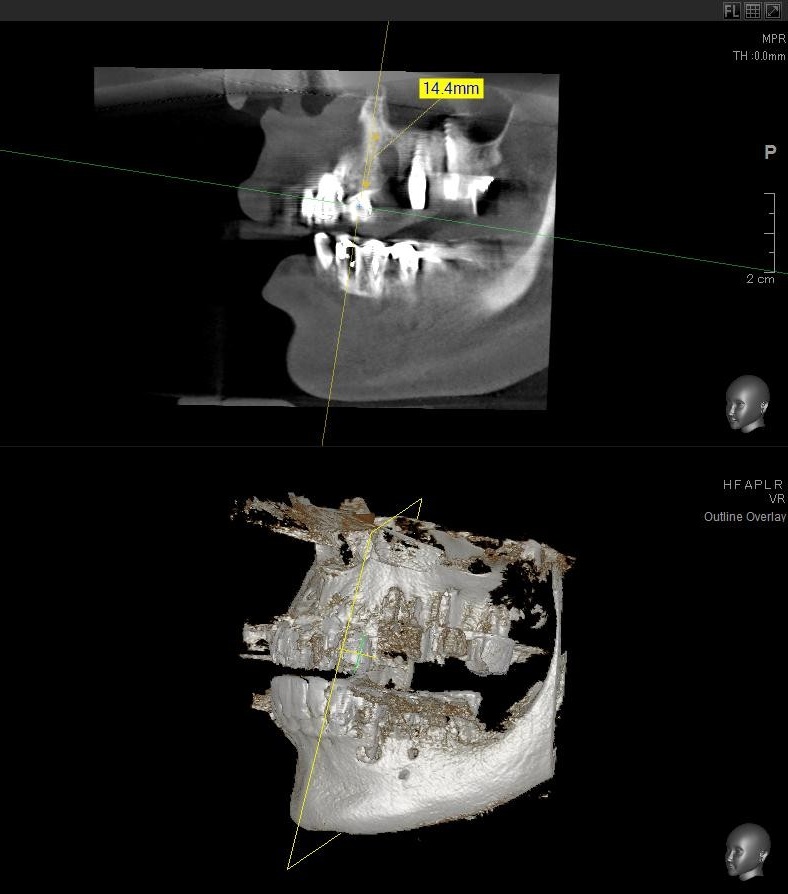

今回の患者様はインプラント植立を希望され、左上3番目の植立が決まりました。

開けた穴に、専用道具を使ってネジを締めるように長さ2センチ程のインプラントを骨に埋め込んでいきます。

しっかりとインプラント埋め込まれた後は、動揺がないか、噛んだ時に当たらないかなどを確認して、最後にパノラマ写真を撮影して今回のオペは終了となりました。